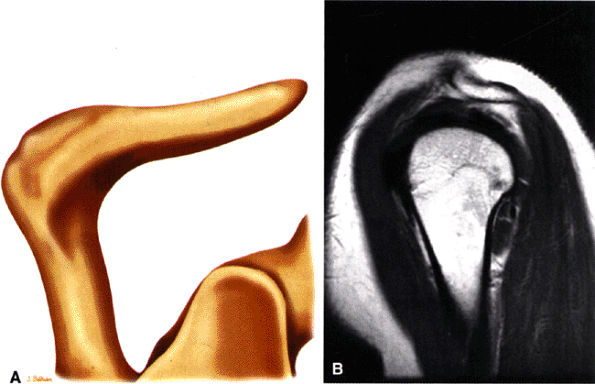

The acromion is classified into several types according to its morphology:

Type 1 (a flat or straight undersurface with a high angle of inclination)

Type 2 (a curved arc and decreased angle of inclination)

Type 3 (hooked anteriorly with a decreased angle of inclination)

Type 4 (upward convexity of the inferior surface) (see also the discussion of the etiology of shoulder impingement syndrome)